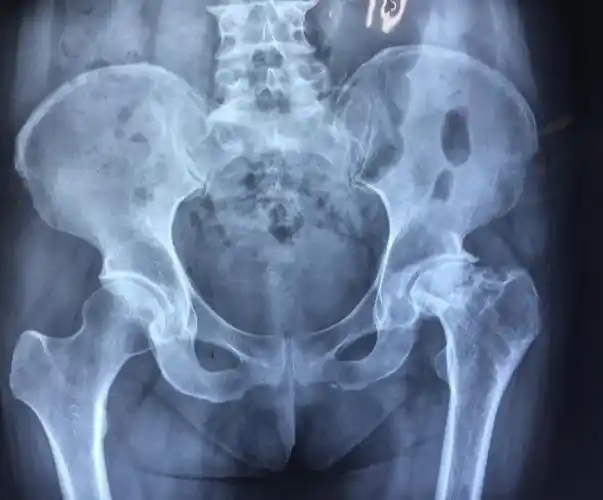

股骨头缺血性坏死的基本知识_股骨头坏死_疾病介绍_介绍 - 好大夫在线

50岁股骨头坏死患者人工全髋关节置换手术一例

双侧股骨头坏死(双侧人工髋关节置换术) - 好大夫在线

骨坏死行空心钉内固定手术,术后发生股骨头骨折

针刀治疗股骨头坏死股骨头塌陷部位已有骨组织

股骨头坏死是如何分期的?哪些患者可以保头?

股骨头坏死(附保髋保股骨头治疗病例)_股骨头坏死_介绍_发病原因_症状